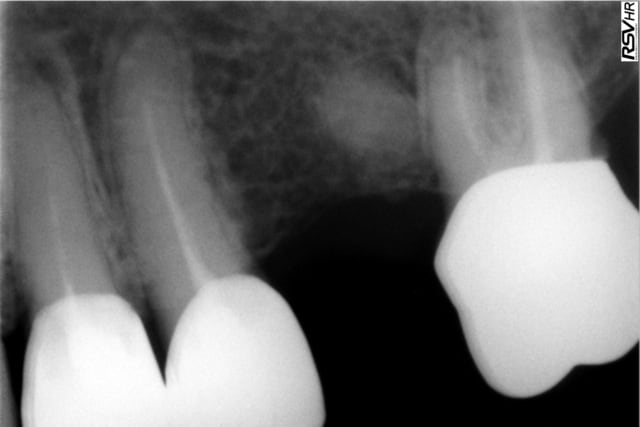

une patiente se présente au mois d'octobre avec plusieurs dents couronnées et des douleurs sur l'une d'elles avec gonflement etc...(ci joint radio préop)

je reprend donc le traitement de la 24 (radio ci jointe), je met la dent d'à coté (asymptomatique) sous surveillance et j'extrait le morceau de racine qui traîne.

j'avais donc plutôt bon espoir mais les douleurs au niveau de cette 24 sont encore presentes avec une legere voussure au niveau du vestibule, moins fortes mais toujours présentes.(radio ci jointe)

question:puis je encore espere une guerison et attendre encore ou dois je re-reprendre le traitement parceque sur la derniere radio les images apicales n'ont pas vraiment disparues????